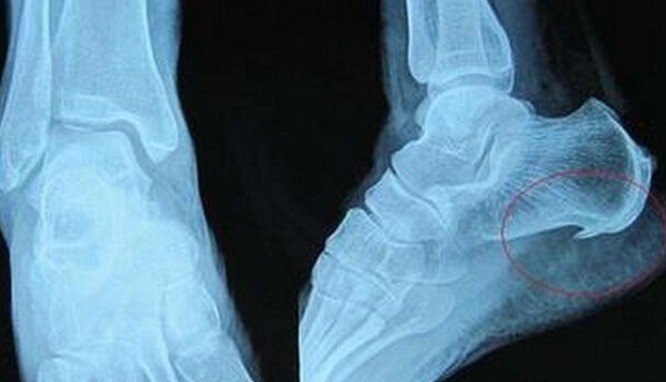

第二种:骨刺骨刺呢其实就是骨质增生。是关节因为种种原因而造成软骨的磨损和破坏。这是一种自然的老化现象,也是咱们人体的一种自我保护。骨刺呢,多发于在45岁以上的中年人或者老年人,而且男性要多于女性,久坐久站的话,也容易会提前诱发骨刺的发生。骨刺这种病,本身是无需治疗的。所以大家千万不要被一些胡乱吹嘘的广告给骗了。